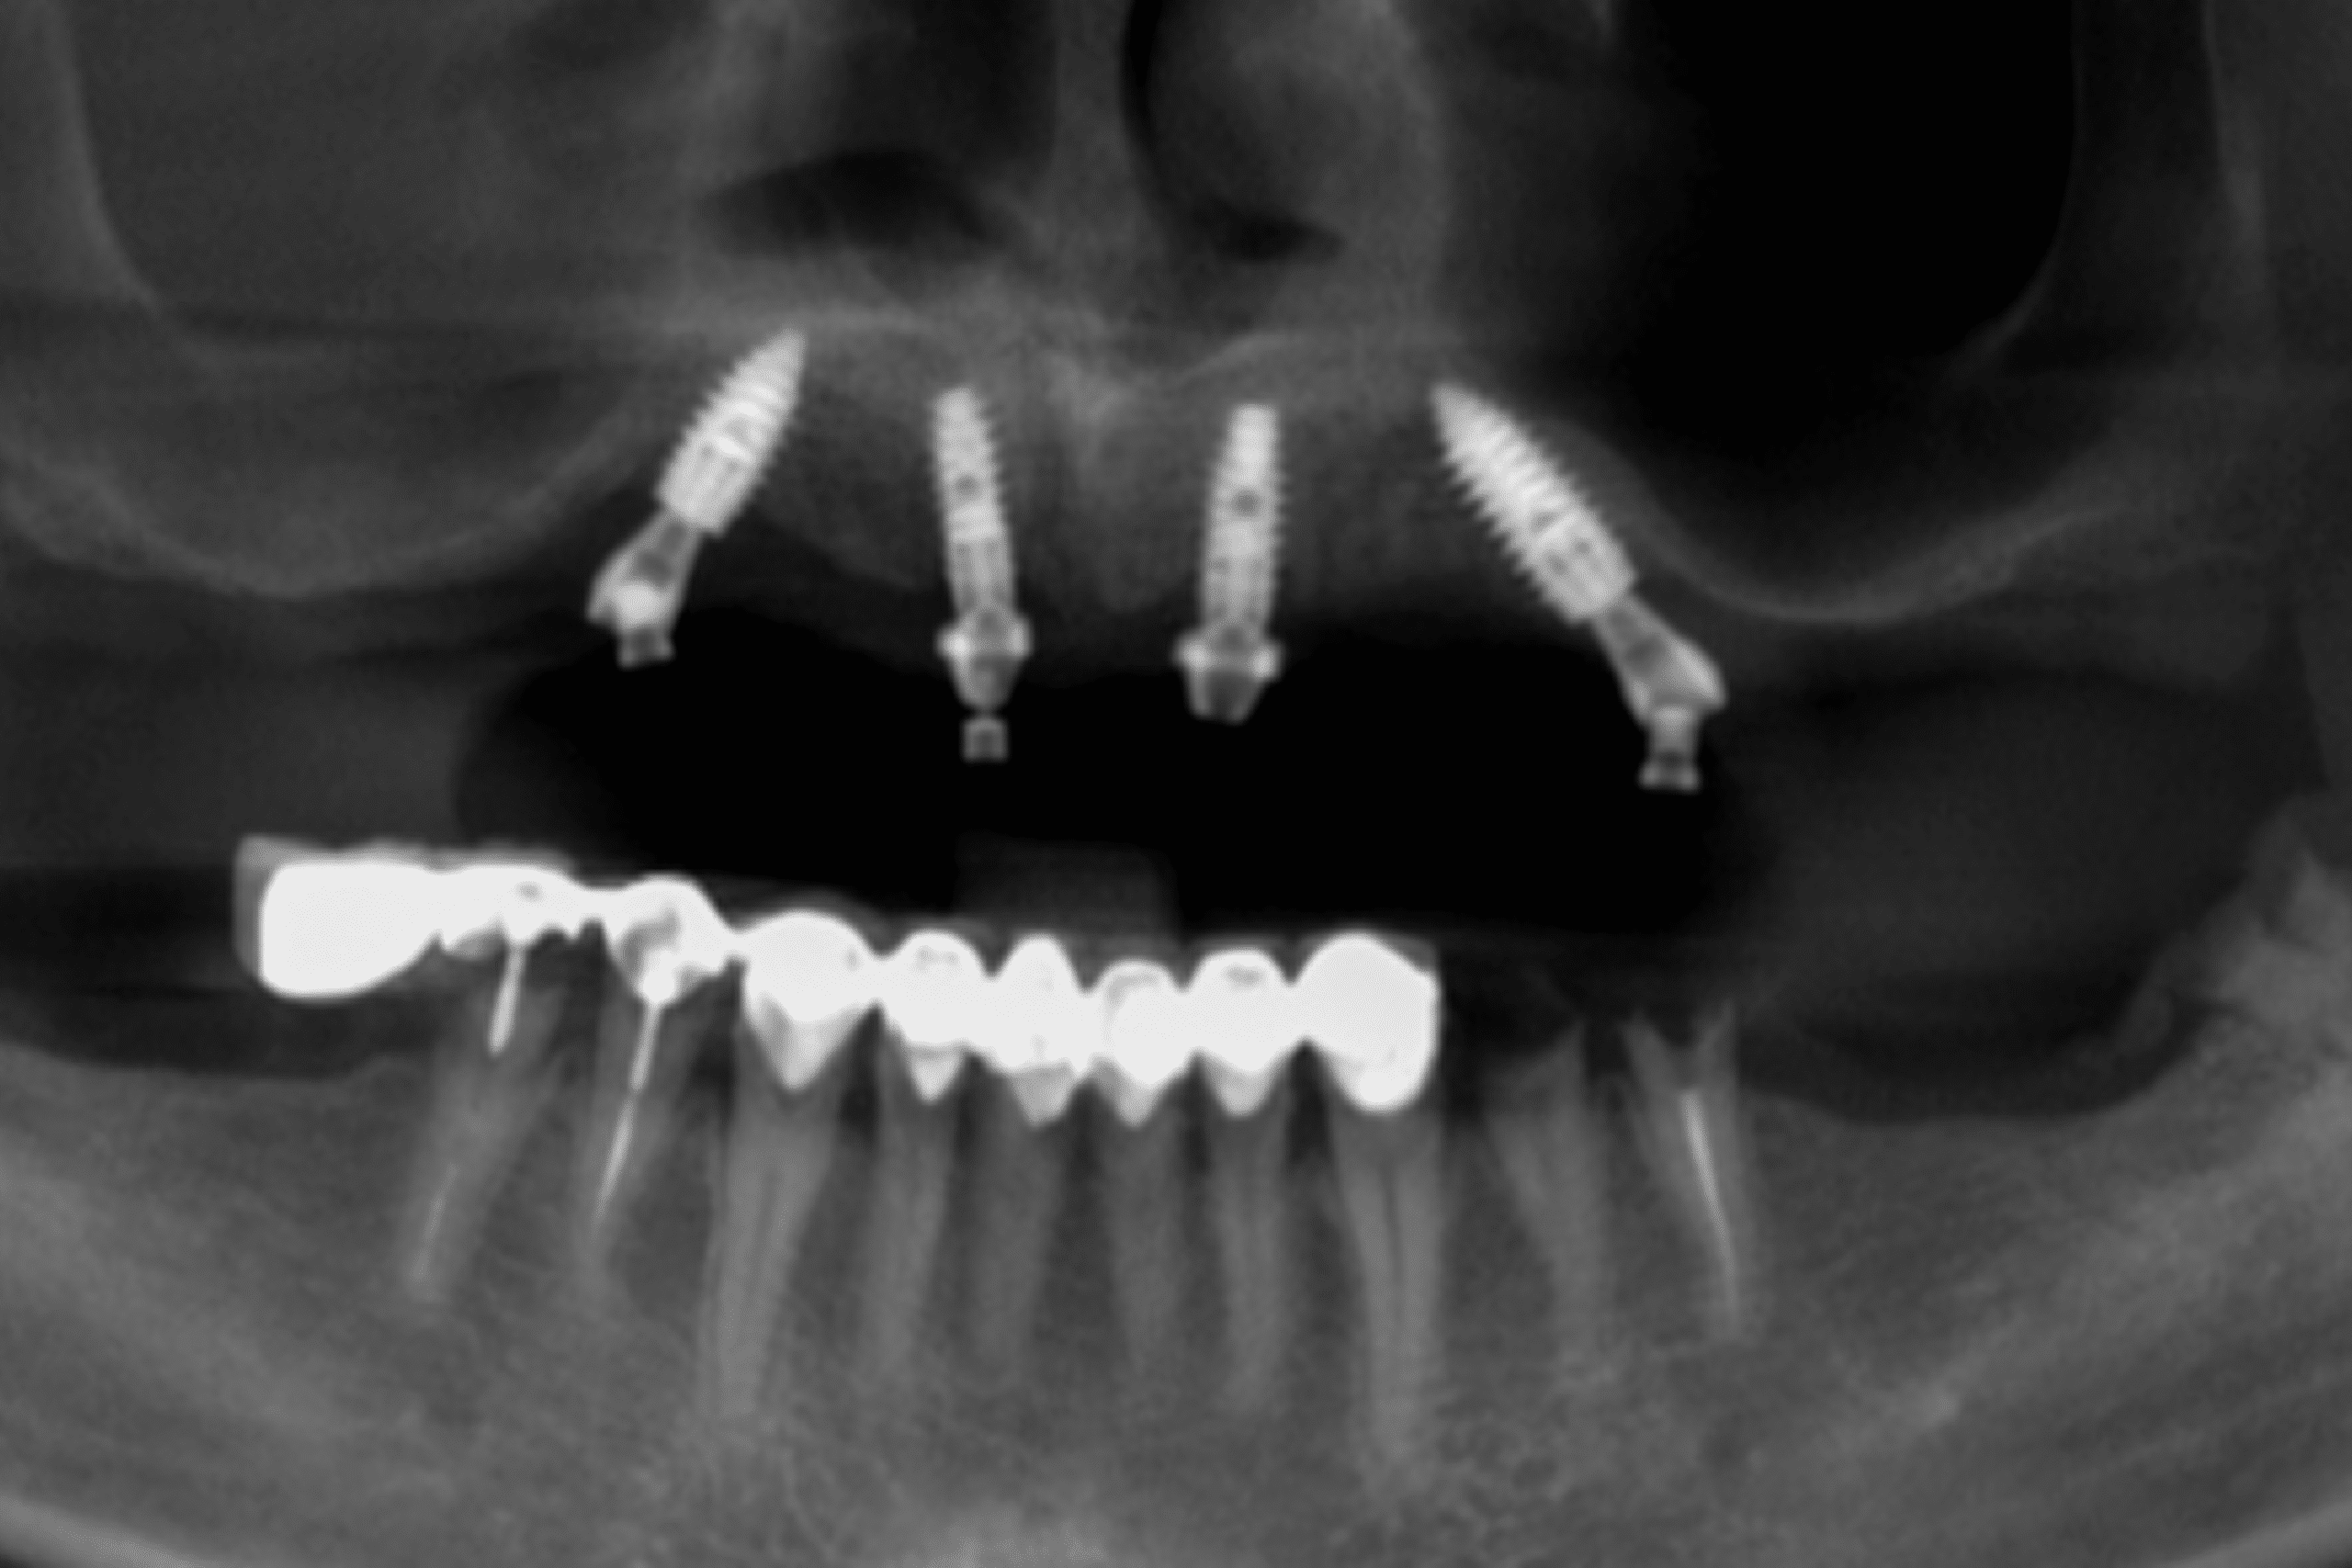

Case 3: Full-Mouth Rehabilitation for James Carter

Complete Upper Jaw Restoration & Lower Jaw Correction with a Flapless Procedure in Just 3 Hours

James Carter presented to our clinic with no remaining upper teeth and a failed lower-jaw restoration that left him unable to chew comfortably or smile with confidence. His condition was affecting both his daily function and overall quality of life, and he was seeking a fast, predictable solution that would restore his oral health without extensive surgical trauma.

Following a full digital assessment and CBCT imaging, our team determined that James was an ideal candidate for a minimally invasive flapless implant procedure — a technique that allows implants to be placed through small, precise openings without the need for incisions or sutures.

- Placement of multiple implants in the upper jaw

In only 3 hours, James received a complete upper-jaw reconstruction and a corrected lower-arch restoration using a fully flapless implant technique.